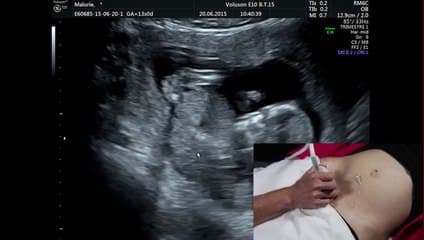

La plus grande ressource vidéo en échographie fœtale de France. Conférences, cours magistraux, démonstrations pratiques et podcasts par les experts du Collège Français d'Échographie Fœtale.

La médiathèque du Collège Français d'Échographie Fœtale (CFEF) constitue l'une des plus importantes collections de ressources vidéo dédiées à l'échographie fœtale en France. Avec plus de 3 261 vidéos, elle couvre l'ensemble des thématiques liées à la pratique échographique prénatale.

Vous y trouverez des conférences présentées lors des congrès nationaux et internationaux, des cours magistraux dispensés par des experts reconnus, des démonstrations pratiques sur des cas cliniques réels, ainsi que des podcasts et tables rondes sur les dernières avancées de la spécialité.